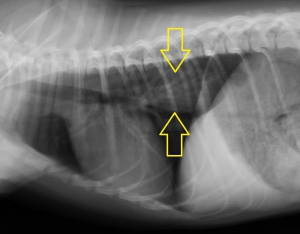

こういった場合、まず、レントゲン検査を行って異物の見当をつけます。下の胸部レントゲン写真で黄色い矢印に挟まれた部分が少し白っぽく見えるのがお分かりでしょうか?実は画像診断ではこういった特徴ですぐに胸部食道の異物を疑うことができます。

下写真は胸部レントゲン検査の画像です。【ケース1】と同様に黄色の矢印の間にわずかに白いエリアが見られます。